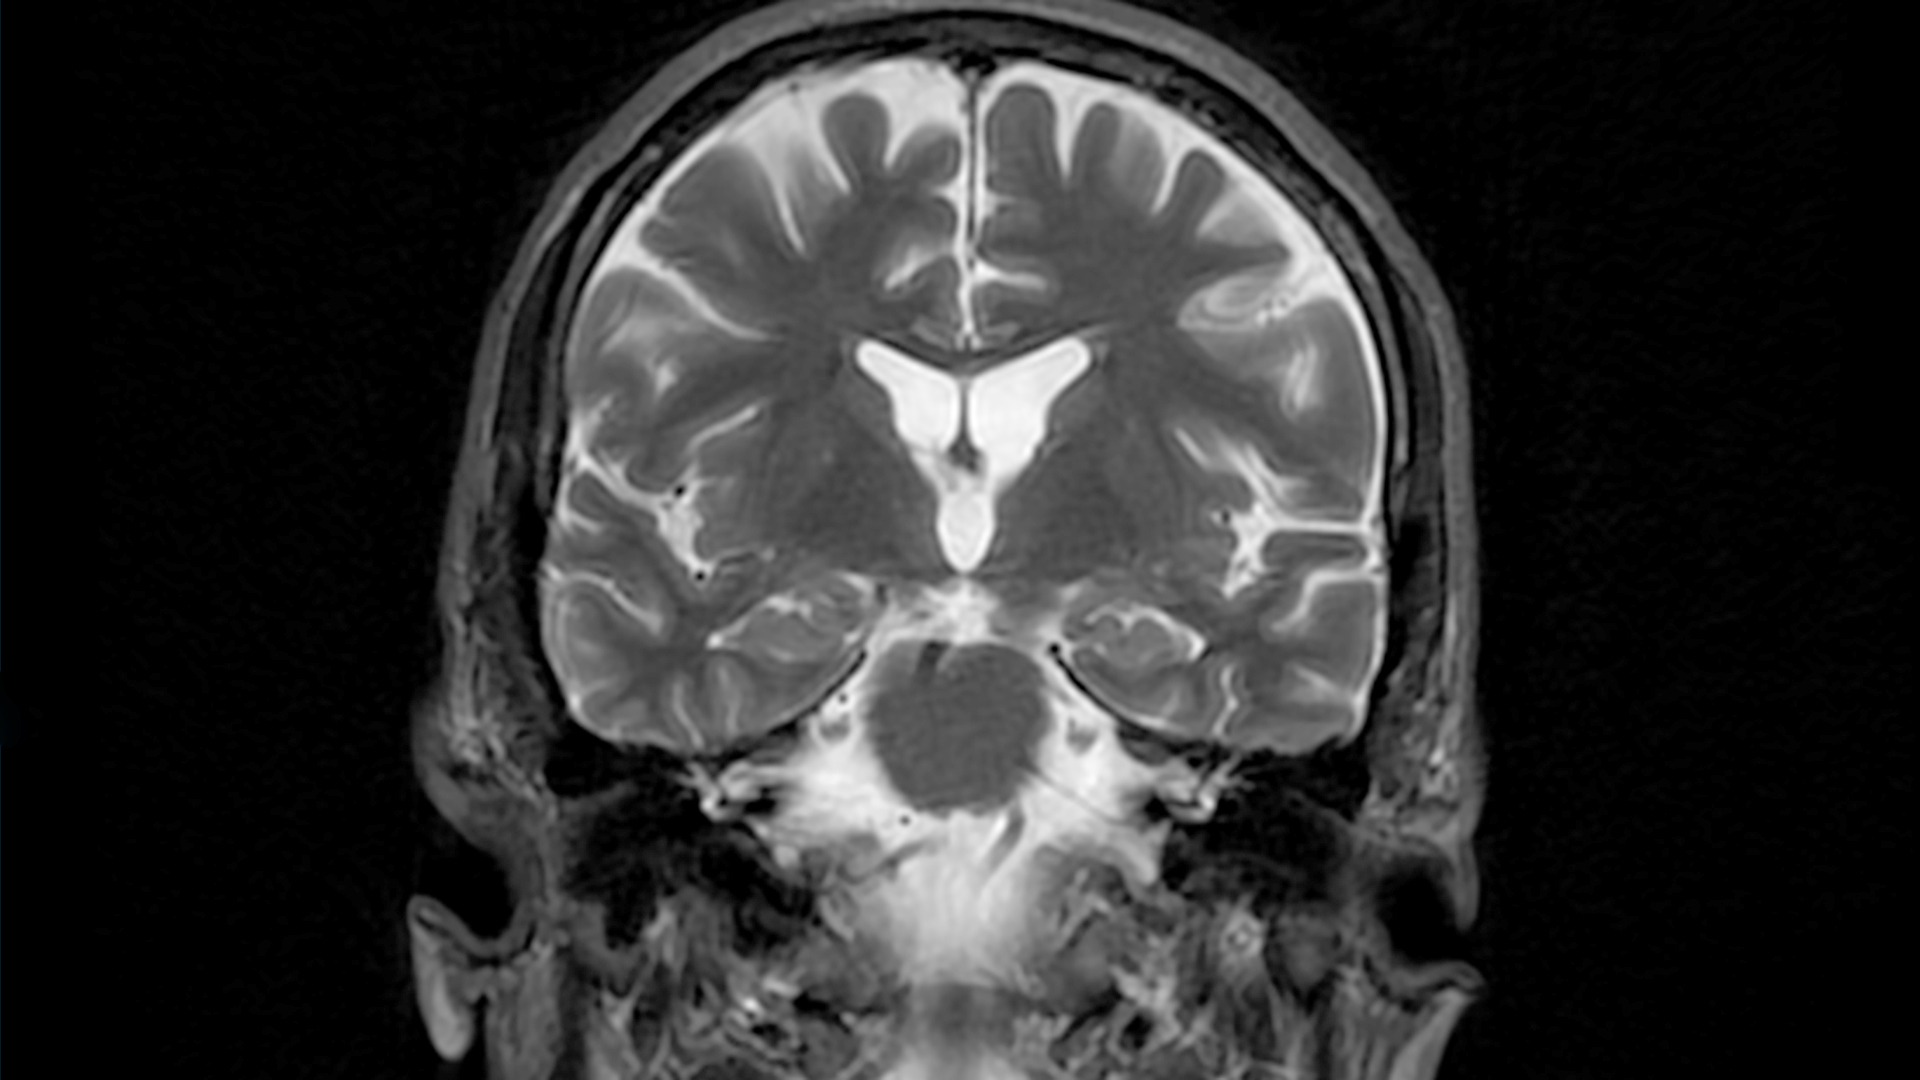

IRM du cerveau de patient atteint de la maladie d’Alzheimer. Une des conséquences de la maladie d’Alzheimer est la formation, dans le cerveau, de plaques extracellulaires riches en métaux : les plaques amyloïdes et les fibrilles tau.

Une des conséquences de la maladie d’Alzheimer est la formation, dans le cerveau, de plaques extracellulaires riches en métaux : les plaques amyloïdes et les fibrilles tau. Les métaux présents dans ces plaques extracellulaires sont notamment le cuivre et le zinc. Les concentrations de ces métaux dans les tissus humains varient naturellement dans le temps, avec l’alimentation par exemple. Les seules mesures de leurs concentrations ne sont donc pas de très bons indicateurs de la formation de ces plaques amyloïdes et fibrilles tau .